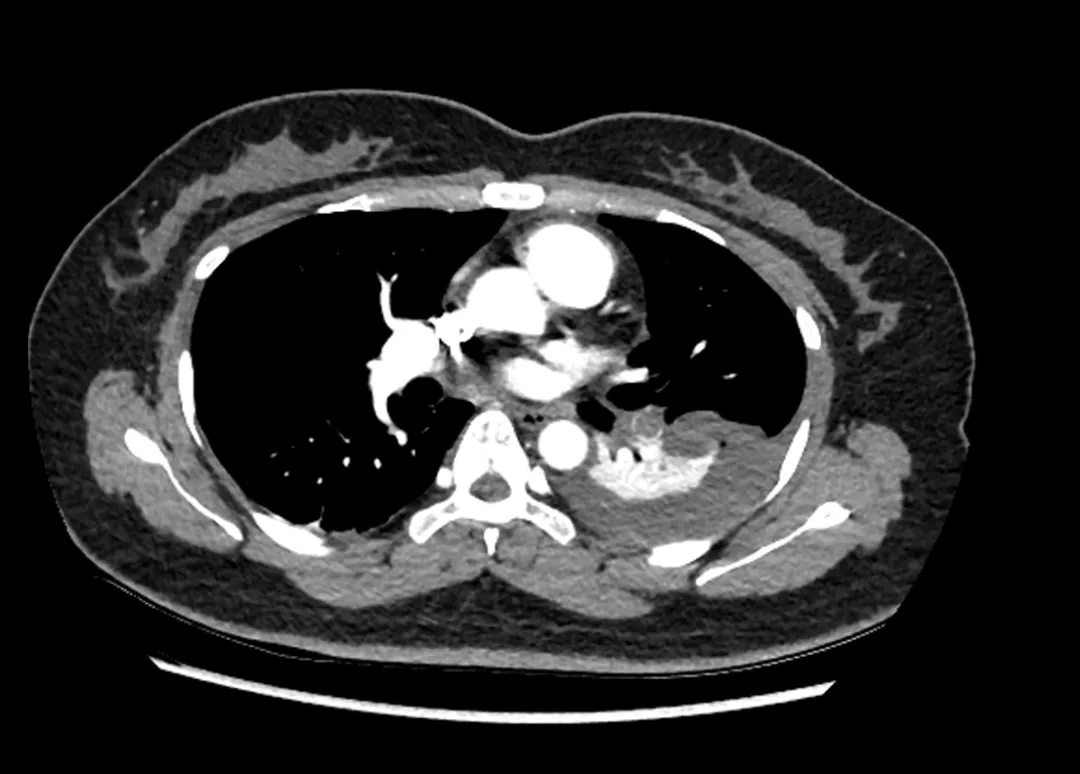

同事立即将她就近送往医院检查,考虑是急性肺栓塞、发生肺部感染,药物治疗后效果不佳,仍然有咳嗽,而且在咳嗽、体位改变的时候胸痛症状加剧。再次到医院复查时发现双肺动脉多发肺栓塞,已经发展成为双肺肺炎、胸腔积液。

经过详细的询问病史和进一步检查之后,呼吸与危重症医学科-肺血管介入组组长洪城主任表示,患者的D二聚体4794 ng/ml,超过正常人的二十多倍,凝血功能亢进,属于易栓症体质,初步诊断考虑是“急性肺栓塞”。

患者入院复查CTPA

面对这种情况,洪城团队迅速调整了治疗方案。首先通过药物治疗减轻胸痛程度,有效降低蛋白C活性,然后结合患者症状明显、肺梗死面积大的病情,为其进行静脉溶栓,密切监测患者D二聚体、纤维蛋白原、心电图等重要指标的变化情况,确保溶栓效果及安全性,溶栓后继续使用普通肝素进行抗凝治疗。

患者影像检查变化

经过规范的溶栓、抗凝治疗,患者咳嗽及咳嗽时胸痛的情况明显好转,复查造影结果显示,肺梗死灶和胸腔积液均有明显改善。